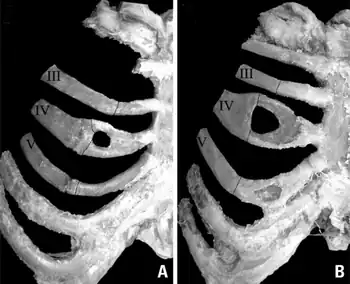

![]() | |